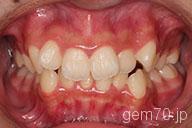

症状:叢生装置:セラミックブラケット | 非抜歯(歯を抜かない)世代:中学生

主訴)歯のでこぼこ

診断)叢生

年齢)14歳

使用装置)マルチブラケット装置

治療方法)非抜歯(歯を抜かない)

治療期間) 2年4ヵ月 通院回数 27回